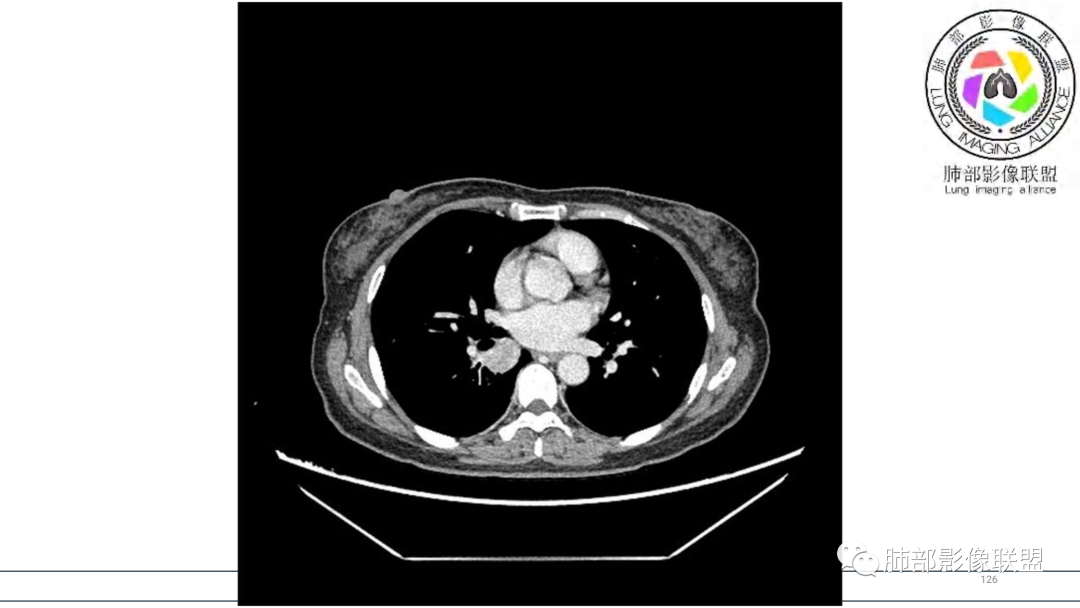

2.右肺下叶及中间段支气管后方类圆形块影,边界较清楚,未见分叶及毛刺,病灶部分突入支气管腔内(冰山一角),局部管腔狭窄,相应肺叶未见片影或体积变化。

3.块影密度均匀,未见液化坏死及钙化,渐进性强化,强化显著。

4.双肺门及纵隔未见增大淋巴结。未见胸腔积液。

中青年女性,支气管管腔内外肿块(“冰山征”),边界较清楚,强化显著,未见阻塞性肺不张,尽管未出现“类癌综合征”临床表现,仍然符合典型类癌影像学表现。